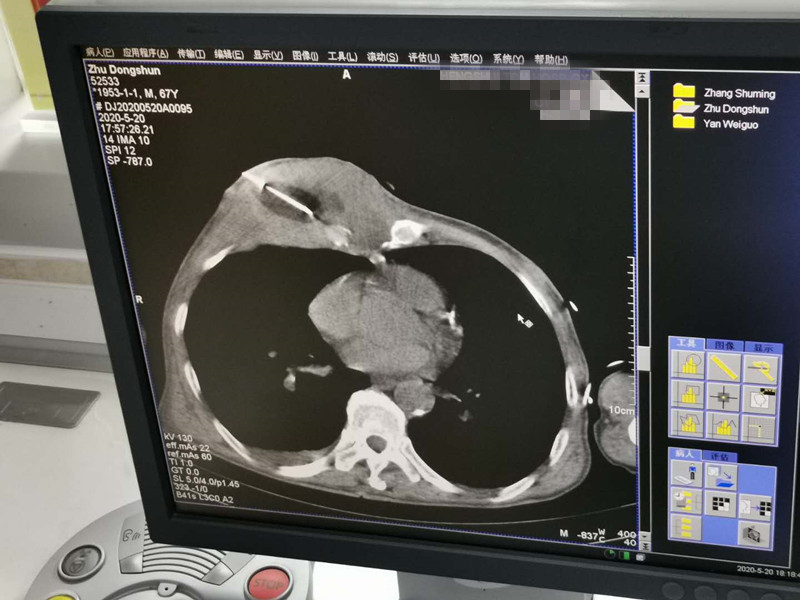

67岁胸部肉瘤氩氦刀冷冻消融

发布人:美国氩氦刀技术官方网站    发布时间:2020/5/21 14:53:37